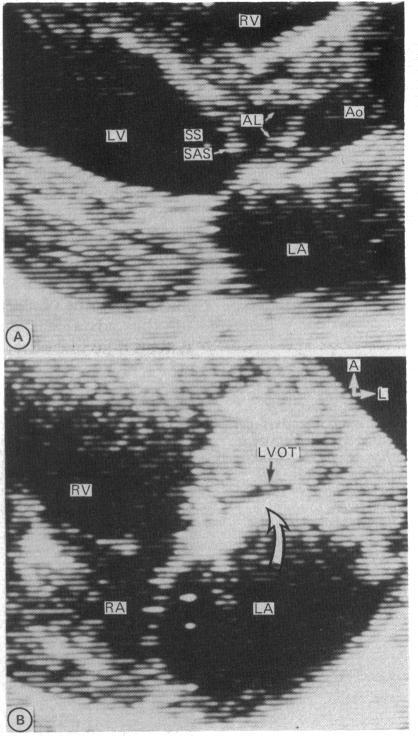

Retrospective echocardiographic review identified 58 consecutive infants and children with fixed subaortic stenosis. Mean (SD) age at diagnosis was 4.8 (3.6) years (range two days to 14.7 years), and diagnosis occurred in infancy in eight. Associated cardiac abnormalities were present in 41 (71%) whereas fixed subaortic stenosis was an isolated lesion in 17 (29%). Four types of fixed subaortic stenosis were identified: short segment (47 (81%)), long segment (7 (12%)), posterior displacement of the infundibular septum with additional discrete narrowing of the left ventricular outflow tract (3 (5%)), and redundant tissue arising from the membranous septum (1 (2%)). Echocardiographic studies had been performed before the diagnosis of fixed subaortic stenosis in nine patients, all with associated abnormalities. These were performed in infancy in each and showed a "normal" left ventricular outflow tract in six and posterior deviation of the infundibular septum in three. In 16 patients serial echocardiographic studies had been performed after the diagnosis of fixed subaortic stenosis but before surgery of the left ventricular outflow tract. Rapid evolution of short segment to long segment narrowing was seen in one patient, and tethering of the aortic valve or mitral valve developed in a further four patients. Aortic valve or mitral valve involvement was not seen before the age of three years but was common thereafter (10/40 patients, 25%). Fixed subaortic stenosis may be an "acquired" lesion with the potential for changes in form as well as progression in severity of left ventricular outflow tract obstruction.